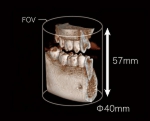

インプラント治療では、骨の深さや密度、インプラントを埋入する角度等が重要になります。

これらの情報をこのシミュレーションによって把握し、より安全で正確に治療進めることで、インプラント治療の成功率を高めています。

3Dでの撮影が可能なため、顎の骨の状態(密度・深さなど)を把握することができます。